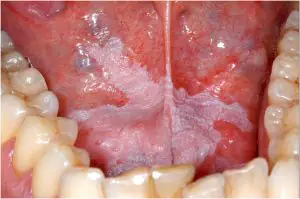

Oral Leukoplakia 2022-08-30 Author-Dr Aparna Pandya (Mrs India Vivacious 2019) Leukoplakia is a white or gray patch that presents itself on the tongue, the inside of cheek, or on

What is Leukoplakia? How does it Occur? 2021-04-06 Do you need to worry about those Thick, White, Grayish Patches formed inside your Mouth? What is Leukoplakia?Leukoplakia is an ailment in which thick